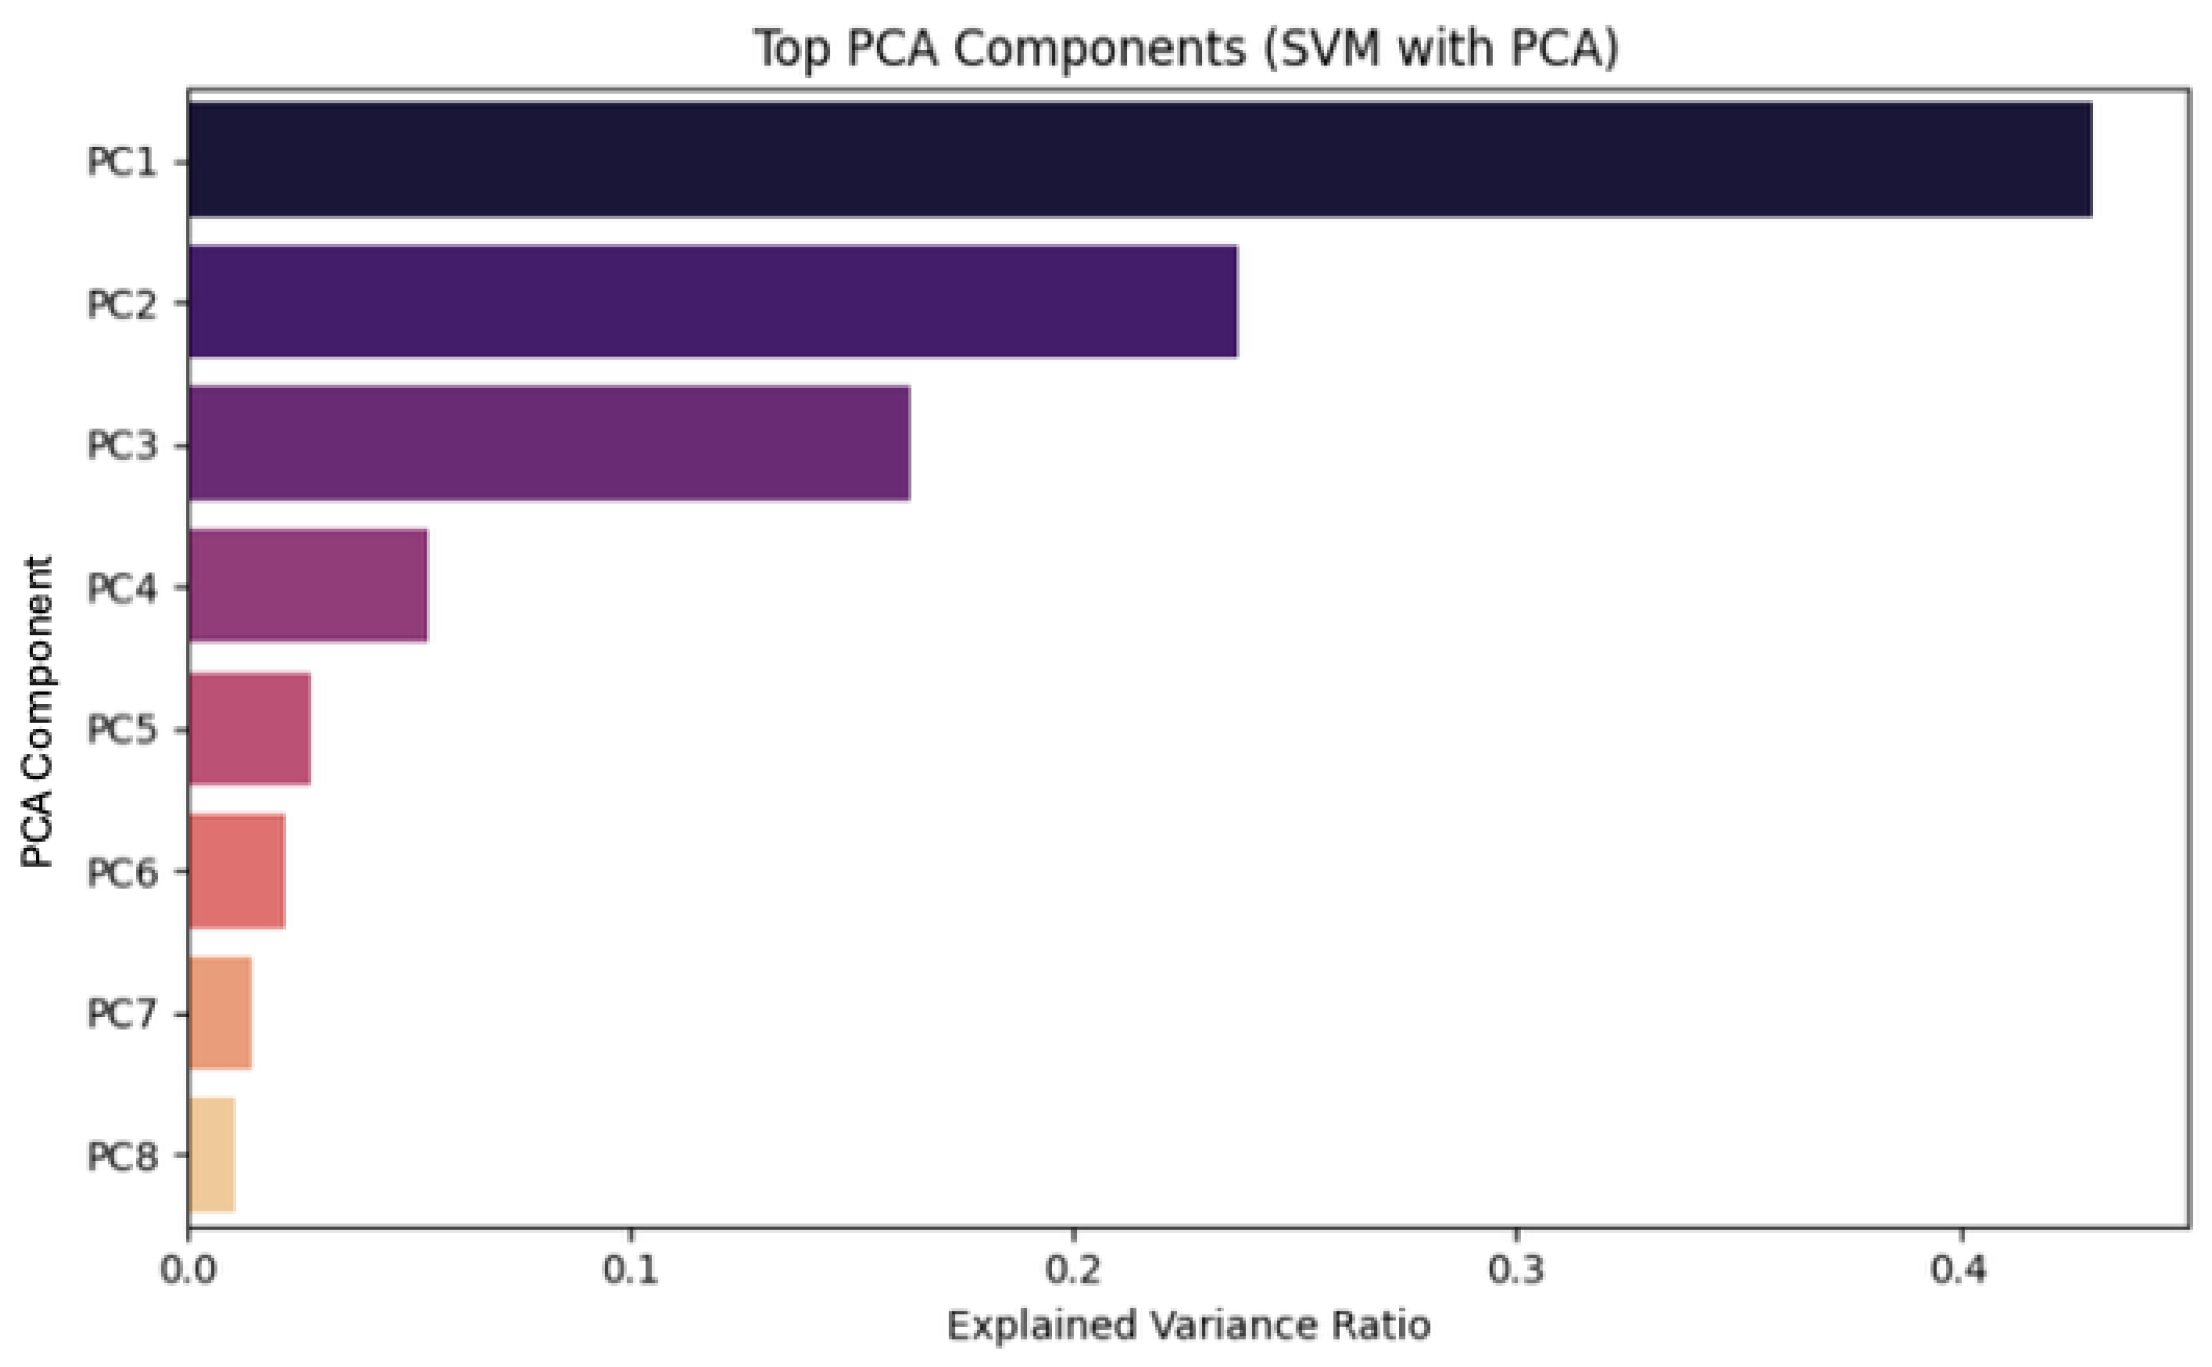

4.1. Dimensionality Reduction

| n_components | 0.90, 0.95, 0.99, None | Number of principal components to keep in PCA if it is an integer. Values between zero and one define the fraction of the total variance that should be preserved. |